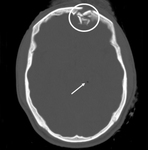

Axial CT scan demonstrating open elevated linear skull fracture (large arrow). Note the air in the soft tissues (small arrow), the small amount of pneumocephalus associated with the fracture (circle), and that the level of elevation of the bone fragment is significantly more than the thickness of the bony table